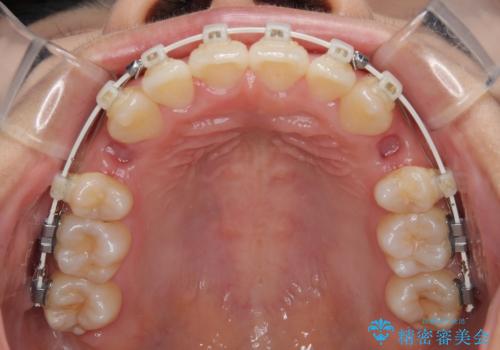

単純に上下左右の第一小臼歯4本を抜歯して口元の突出感を改善することも考えられましたが、上顎骨よりも下顎骨の幅が広いため、より良い咬み合わせを達成することを目的として、急速拡大装置を用いて上顎骨を拡大することとしました。

歯列矯正では基本的に骨格を改善することはできませんが、急速拡大装置(MARPE)を使用することで上顎骨を側方に拡大させることができ、咬合状態を大きく改善することができます。